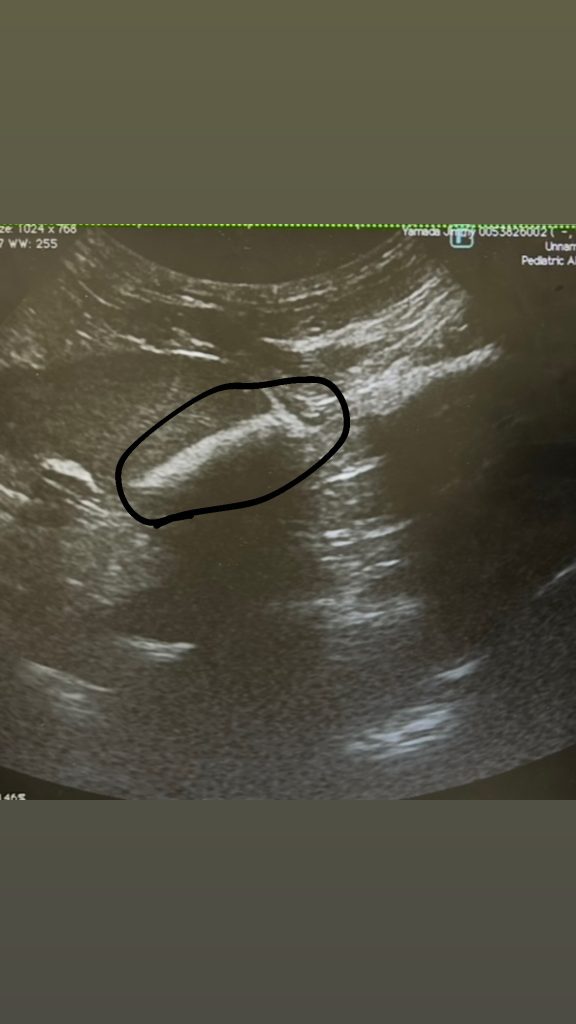

でこれが今日の膀胱。

減ってた!砂減ってた!!

の割にお尻にしっこがつくのが気になったんやけど、先生曰く「多分、おしっこと一緒に砂が出てるんじゃないか。だからシャーって出るんじゃなくちょっと周りの毛につくんじゃないか。」て事で結果は良かったー!!